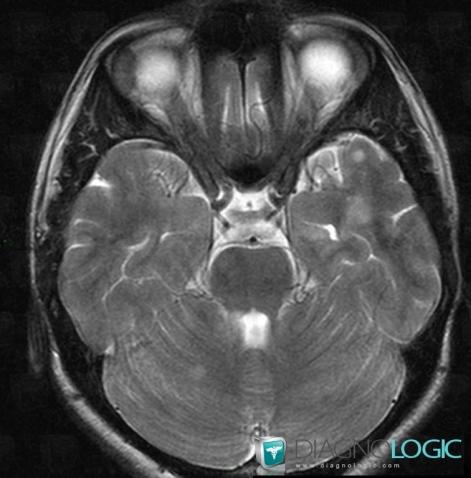

Multiple sclerosis, Posterior fossa, MRI

Here is the specific information in the key image above:

- Diagnosis Multiple sclerosis, Location(s) Posterior fossa, with gamuts Multifocal infratentorial lesions, Infratentorial T2W or FLAIR hyperintense lesion